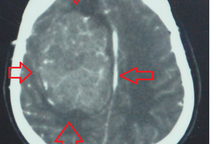

Người mắc bệnh động kinh có những biểu hiện sớm như có những cơn co giật, sùi bọt mép, chớp mắt/nháy mắt liên tục, hay tê bì tay chân, nóng dưới ngực rồi lan lên trên… Họ thường có những cơn co giật hàng ngày khoảng 5-10 cơn, mỗi cơn co giật 1-5 phút. Thường những người mắc bệnh ở giai đoạn đầu với biểu hiện tổn thương ở bán cầu não trái hoặc phải.

Nếu không điều trị sớm, trong vòng 5-10 năm tiếp theo phần tổn thương sẽ tiếp tục lan sang phần bán cầu não còn lại gây ra tổn thương não với những ổ tổn thương diện rộng phát nhiều cơn động kinh hơn. Khi đó, tỷ lệ khỏi bệnh sẽ khó khăn hơn nhiều, PGS Hệ cho biết.